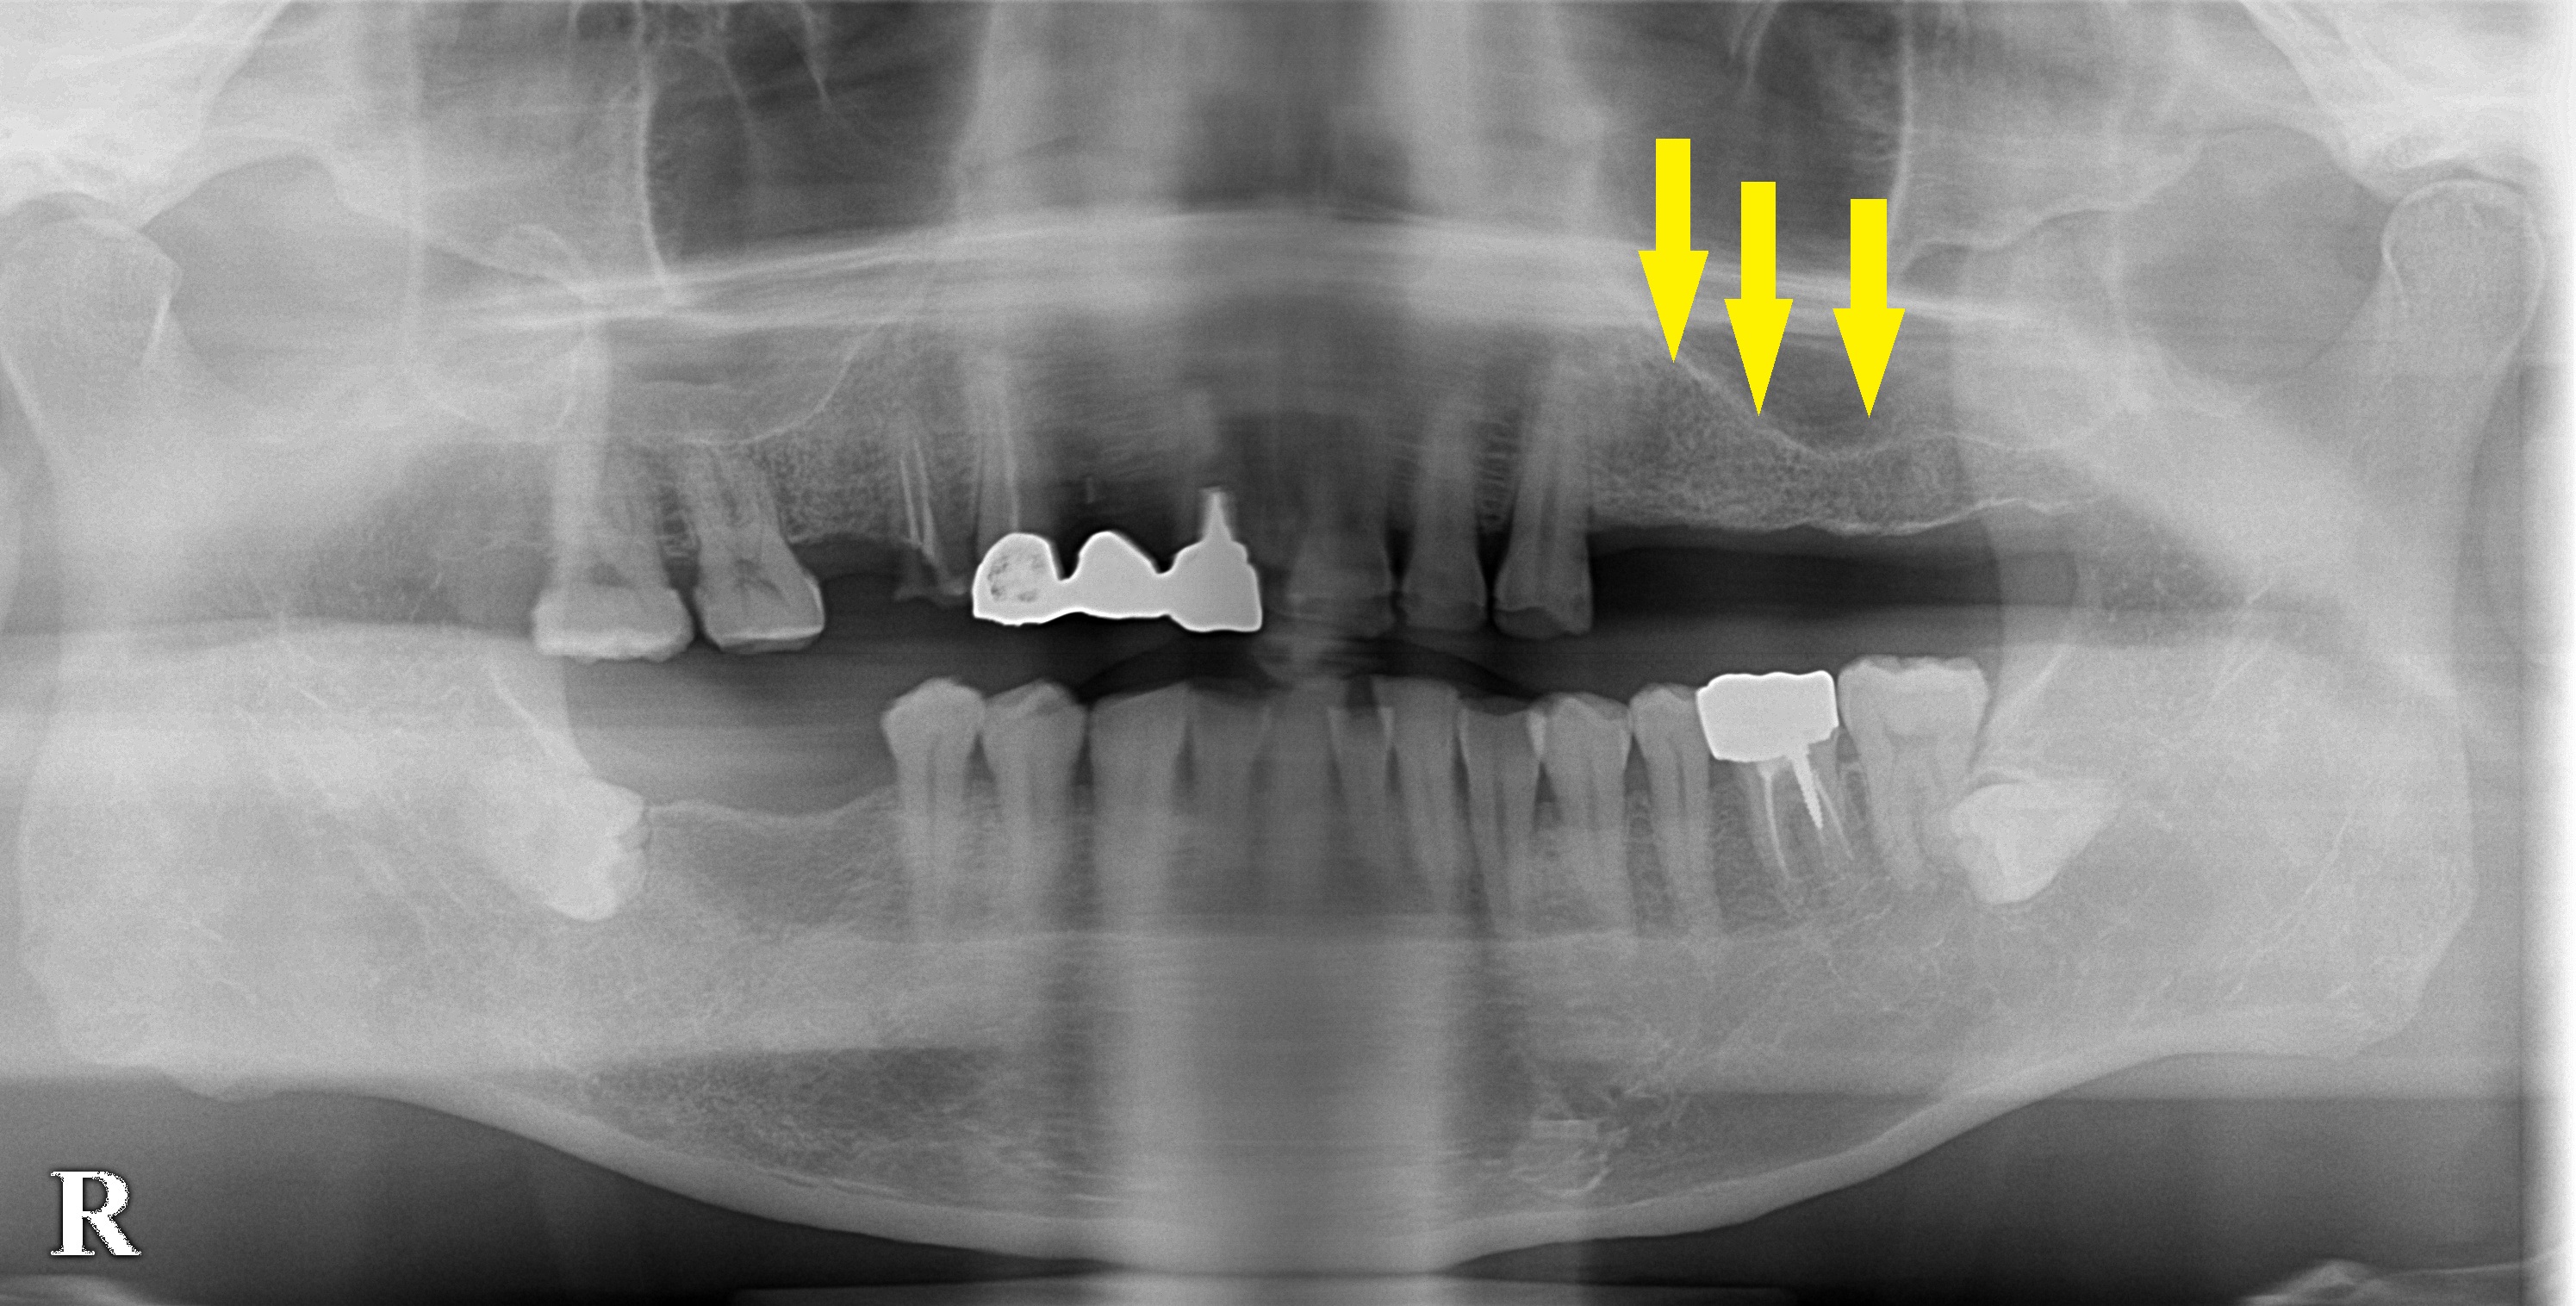

レントゲン、CTにて、2本目と3本目は骨の高さが不足していましたので、本日ソケットリフトという骨造成術を併用して、3本のインプラント埋入術を行いました。

CT画像|インプラント治療で選ばれる名古屋の歯科医院